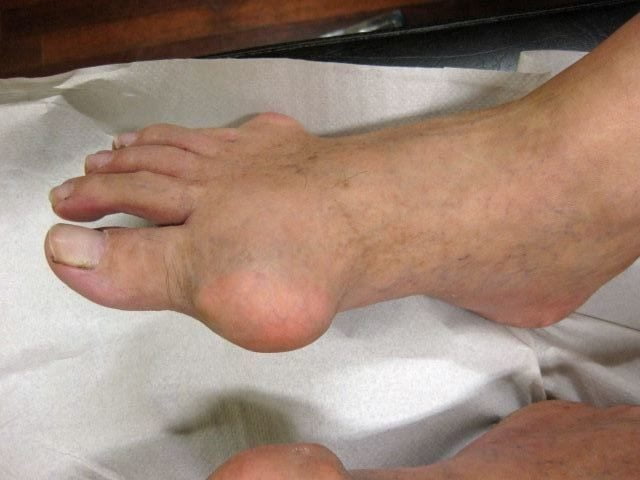

Основной симптом артрита большого пальца стопы — воспаление, которое заметно для невооруженного глаза. Оно сопровождается болью, отечностью, опуханием, покраснением, повышением температуры в зоне поражения. Еще одним симптомом патологии является жесткость в суставной полости. Обычно она появляется утром и постепенно исчезает, когда больной выполняет свою повседневную работу. Со временем из-за постепенного ухудшения состояния может возникать деформация пораженных суставов.

Наибольший дискомфорт вызывает воспаление сустава большого пальца ноги и периартриты стопы. В таком состоянии человек не способен носить обычную обувь, так как нога начинает сильно отекать и появляется сильная боль, отвлекающая от обычной деятельности. По мере развития нарушения увеличивается риск полной потери двигательных способностей и ходьбы.

Артрит, вызванный ревматизмом, может привести к поражению всех суставов. При постоянном воспалении, со временем суставы начинают деформироваться, и возникает в них боль даже в состоянии полного покоя. На большом пальце ноги у человека может появиться нарост в виде шишек, или выросшей косточки, либо даже может измениться ось сустава. Это говорит о запущенной болезни и разрушении сустава у основания пальца, накоплении в суставах солей мочевой кислоты.

Воспаление большого пальца на ноге в начальных стадиях протекает латентно. При прогрессировании болезни пациенты обращают внимание на то, что сустав воспалился, сильно болит и опух. Вырастает болезненная шишка плотной консистенции, она значительно деформирует сустав большого пальца, мешает свободно перемещаться.

Вырост горячий на ощупь, с покрасневшей кожей, нередко достигает 2—3 см в диаметре. При ощупывании боль заметно усиливается, воспаление переходит на соседние зоны. Отек и болевой приступ при отсутствии лечения распространяется на всю стопу. Боль в суставе усиливается при нагрузке и вскоре становится постоянной. Воспаление сопровождается следующими характерными признаками, такими как:

- болевой синдром,

- ограничение подвижности,

- отечность большого пальца с переходом на стопу,

- местная гипертермия и покраснение,

- затрудненность движений.